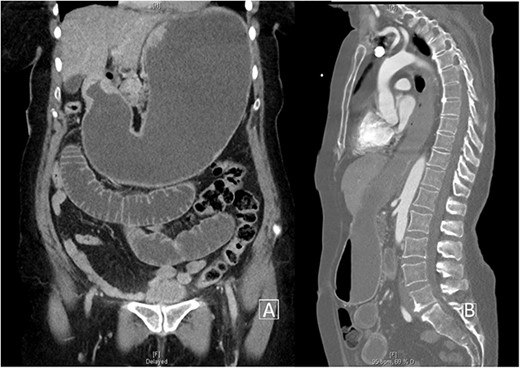

Her initial biochemistry, including high-sensitivity troponin, was within normal limits. A transthoracic echocardiogram showed normal ejection fraction and no segmental wall motion abnormality. She underwent coronary artery catheterization for persistent ST-elevation after thrombolysis, which found only mild non-obstructive coronary artery disease. Due to persisting pain, a computerized tomography (CT) aortogram was performed, demonstrating a significantly dilated stomach, a hiatus hernia and small bowel loops with a transition point suggestive of small bowel obstruction as shown in Fig. 2. Inserting a nasogastric tube for decompression led to significant pain relief and sustained ST-segment elevation (STE) resolution, as shown in Fig. 1B.

(A) Coronal CT cross-section demonstrating gross bowel and stomach distension. (B) Sagittal CT cross-section demonstrating obstruction and reflux of stomach contents into oesophagus.